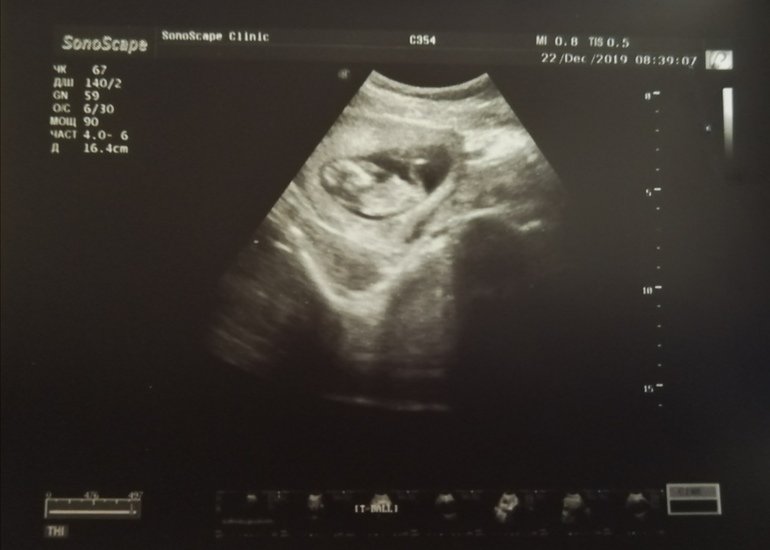

Внеплановое УЗИ. Наш малыш растёт🤰🏻

УЗИ, КТГ, доплерВ связи с тем, что ТТГ у меня повышен (5,8), резко перестала болеть грудь, пропала тошнота, а вчера к вечеру ещё и грудь сдулась, то я конкретно распереживалась, накрутила себя и мужа, всю ночь думала о том, всё ли хорошо с малышом. С утра пошла сдавать кровь на ТТГ (посмотреть есть ли прогресс спустя 2 недели), не выдержала и решила сходить ещё и на УЗИ, чтобы убедиться что всё в порядке. Сделали. Я безумно рада, что всё отлично! Когда врач повернула мне экран, включила СБ и показала, как наше чудо кувыркается у меня в животике, сразу отступило чувство тревоги и наступило спокойствие. ЧСС 171 ритмичное, в пределах нормы, беременность 11-12 недель. Теперь спокойно ждём скрининга. Сделали фото на память и вот такие мы уже большие🥰

*Насчёт пропавших признаков беременности врач сказала, что это нормально, 1 триместр подходит к концу и уровень гормонов приходит в норму.